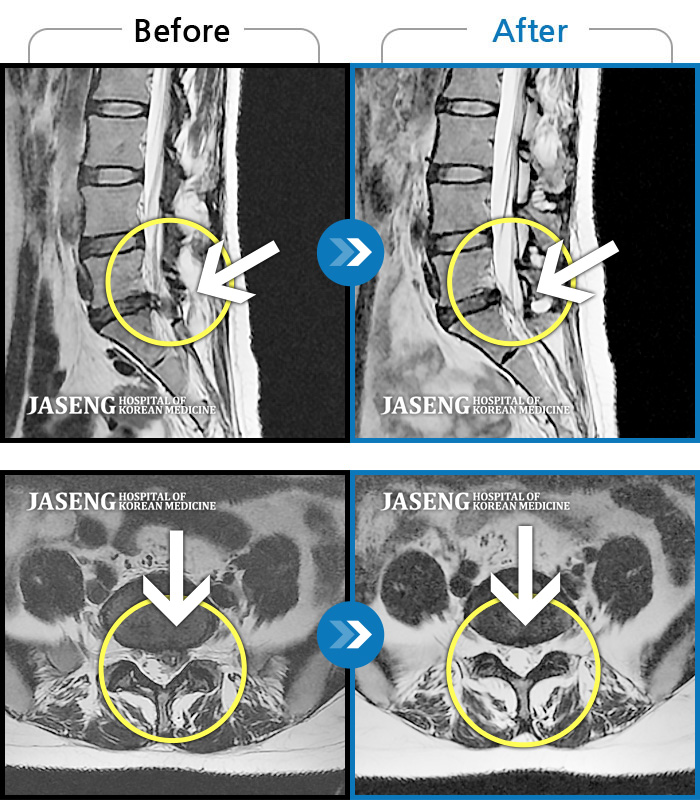

MRI 치료사례

좌측 엉덩이 통증 및 허벅지 당김 증상